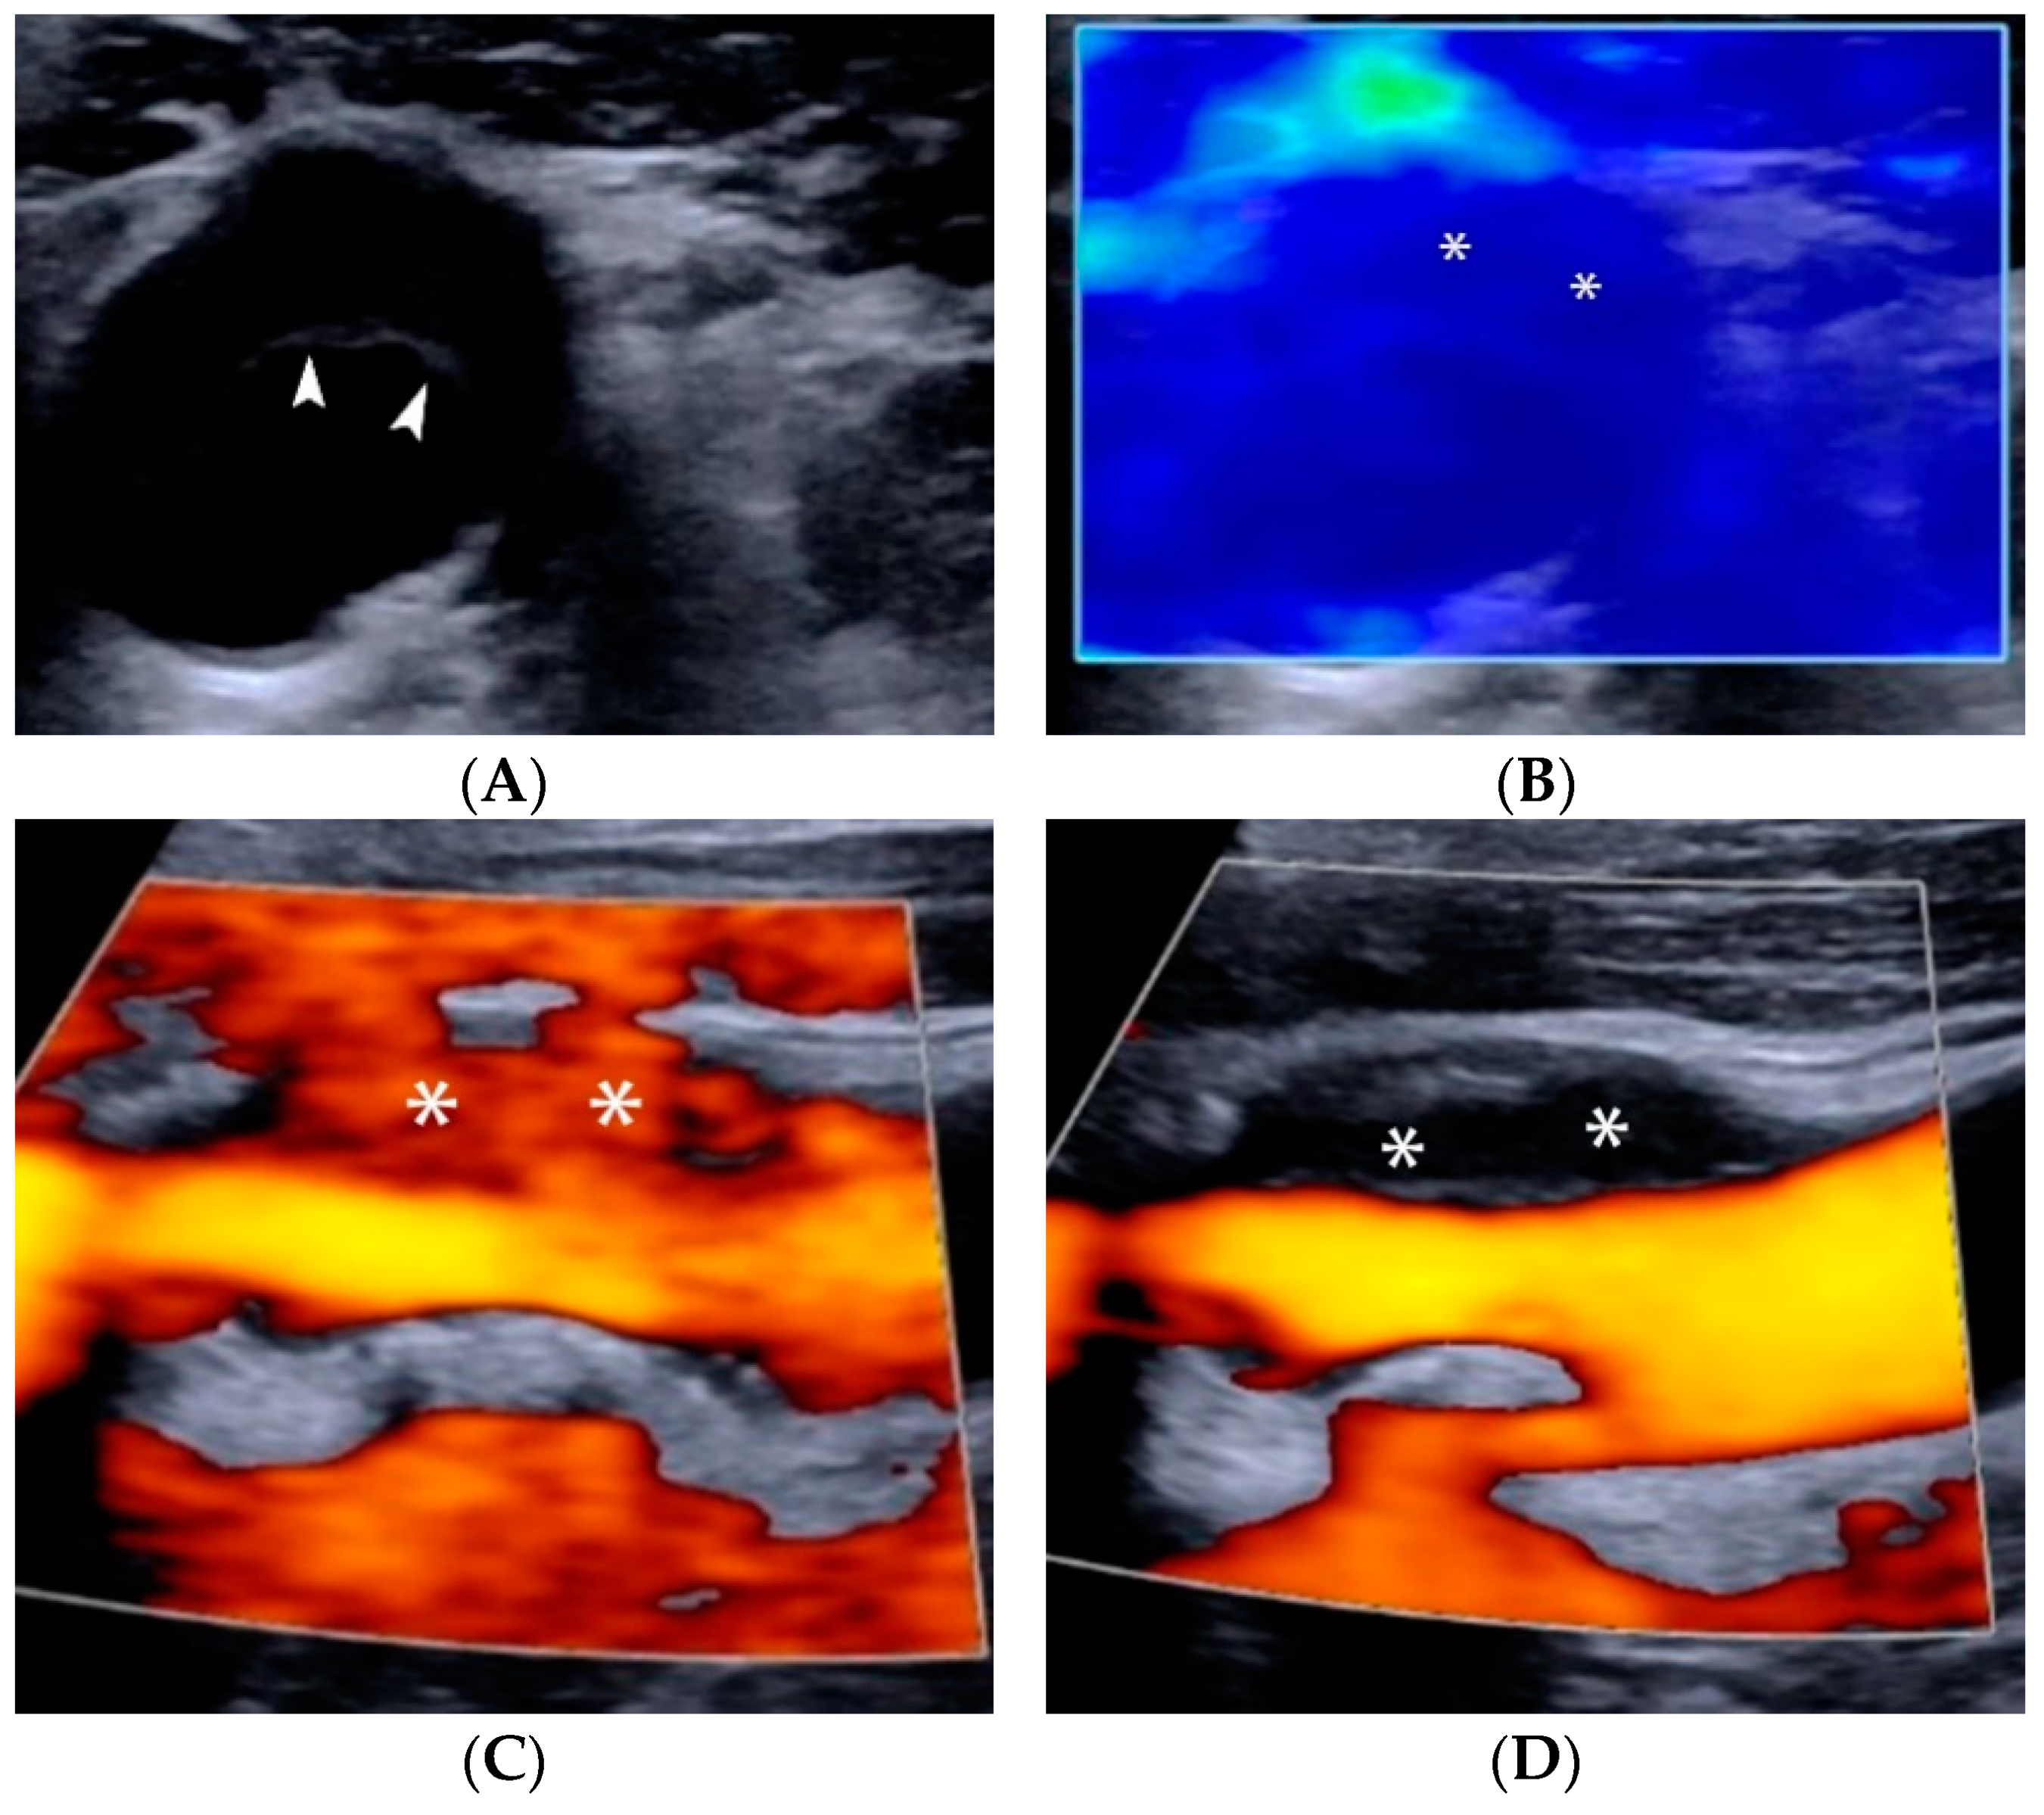

4.1.1. Intraplaque Neovascularization

- Huang, R.; Abdelmoneim, S.S.; Ball, C.A.; Nhola, L.F.; Farrell, A.M.; Feinstein, S.; Mulvagh, S.L. Detection of Carotid Atherosclerotic Plaque Neovascularization Using Contrast Enhanced Ultrasound: A Systematic Review and Meta-Analysis of Diagnostic Accuracy Studies. J. Am. Soc. Echocardiogr. Off. Publ. Am. Soc. Echocardiogr. 2016, 29, 491–502. [Google Scholar] [CrossRef] [PubMed]

- Shah, F.; Balan, P.; Weinberg, M.; Reddy, V.; Neems, R.; Feinstein, M.; Dainauskas, J.; Meyer, P.; Goldin, M.; Feinstein, S.B. Contrast-enhanced ultrasound imaging of atherosclerotic carotid plaque neovascularization: A new surrogate marker of atherosclerosis? Vasc. Med. 2007, 12, 291–297. [Google Scholar] [CrossRef] [PubMed]

- Li, C.; He, W.; Guo, D.; Chen, L.; Jin, X.; Wang, W.; Huang, B.; Wang, W. Quantification of carotid plaque neovascularization using contrast-enhanced ultrasound with histopathologic validation. Ultrasound Med. Biol. 2014, 40, 1827–1833. [Google Scholar] [CrossRef] [PubMed]

- Van den Oord, S.C.; Akkus, Z.; Bosch, J.G.; Hoogi, A.; ten Kate, G.L.; Renaud, G.; Sijbrands, E.J.; Verhagen, H.J.; van der Lugt, A.; Adam, D.; et al. Quantitative contrast-enhanced ultrasound of intraplaque neovascularization in patients with carotid atherosclerosis. Ultraschall Med. 2015, 36, 154–161. [Google Scholar] [CrossRef]

- Hoogi, A.; Adam, D.; Hoffman, A.; Kerner, H.; Reisner, S.; Gaitini, D. Carotid plaque vulnerability: Quantification of neovascularization on contrast-enhanced ultrasound with histopathologic correlation. Am. J. Roentgenol. 2011, 196, 431–436. [Google Scholar] [CrossRef] [PubMed]

- Schinkel, A.F.L.; Bosch, J.G.; Staub, D.; Adam, D.; Feinstein, S.B. Contrast-Enhanced Ultrasound to Assess Carotid Intraplaque Neovascularization. Ultrasound Med. Biol. 2020, 46, 466–478. [Google Scholar] [CrossRef] [PubMed]